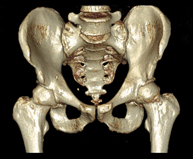

- TC Pelvis ósea Exploración radiológica que mediante un sistema de rayos X y detectores que giran alrededor del paciente, reconstruyendo las imágenes por ordenador (TC Multidetector), permite el estudio de huesos, músculos y articulaciones de la pelvis. Exploración radiológica que mediante un sistema de rayos X y detectores que giran alrededor del paciente, reconstruyendo las imágenes por ordenador (TC Multidetector), permite el estudio de huesos, músculos y articulaciones de la pelvis.

- TC Caderas Exploración radiológica que mediante un sistema de rayos X y detectores que giran alrededor del paciente, reconstruyendo las imágenes por ordenador (TC Multidetector), permite el estudio de huesos, músculos y articulaciones de la cadera. Exploración radiológica que mediante un sistema de rayos X y detectores que giran alrededor del paciente, reconstruyendo las imágenes por ordenador (TC Multidetector), permite el estudio de huesos, músculos y articulaciones de la cadera.